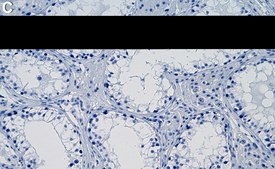

Immunohistochemistry (Paraffin) Analysis: A 1:100 dilution from a representative lot detected ZC3H13 in human testis tissue sections.